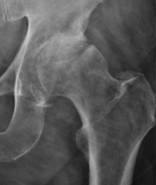

Note: (1) the progressive roughening of the round ball and its socket,

(2) the decreasing clear space (cartilage and fluid) between them,

(3) and the extra rough bone (white material) around the joint.

https://commons.wikimedia.org/wiki/File:X-ray_of_hip_osteoarthritis.jpg

Description English: For context, see: en:Hip pain

Source (2016).

"Imaging of Hip Pain: From Radiography to Cross-Sectional Imaging

Techniques". Radiology

Research and Practice 2016: 1–15. DOI:10.1155/2016/6369237.

ISSN 2090-1941.